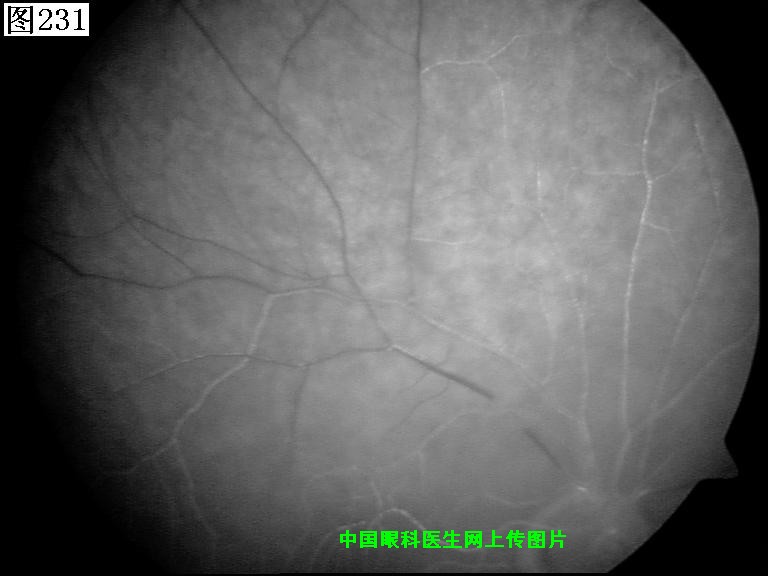

229 230 231 232